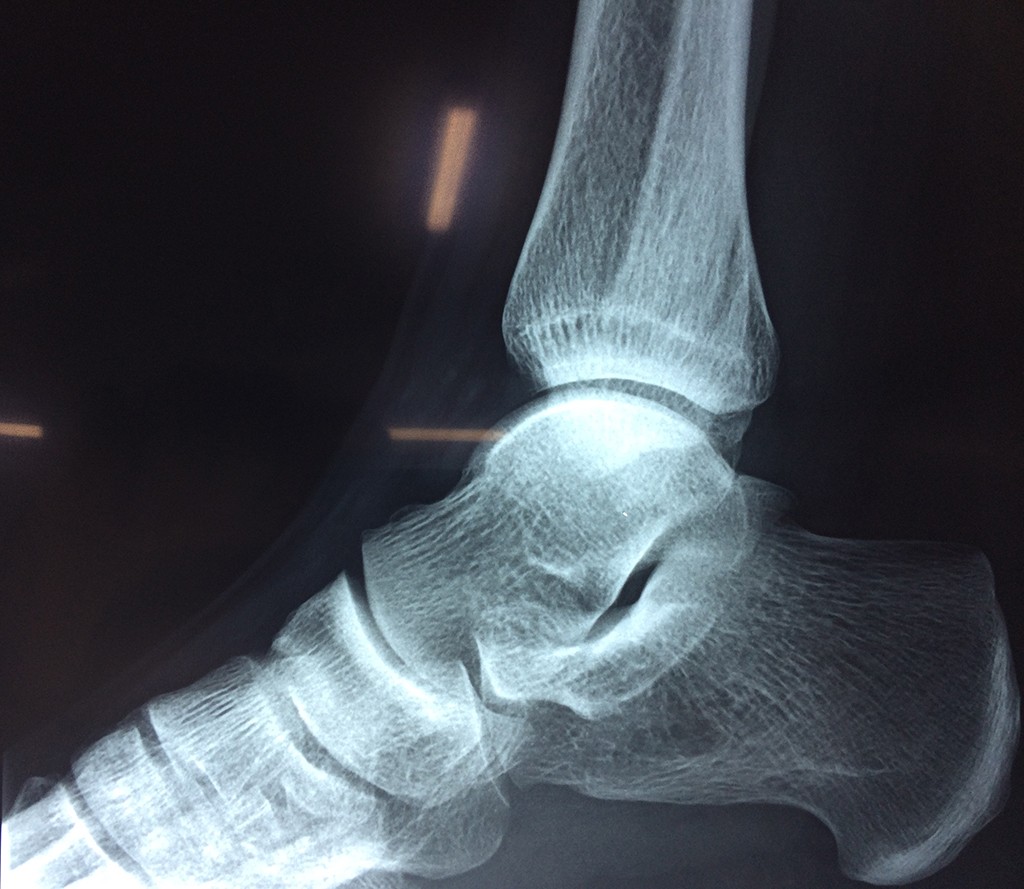

Una fractura de tobillo es la rotura de uno o más de los huesos del tobillo. Estas fracturas pueden ser:

Algunas fracturas de tobillo pueden requerir cirugía si:

- La fractura se extiende hasta la articulación del tobillo (fractura intra-articular).